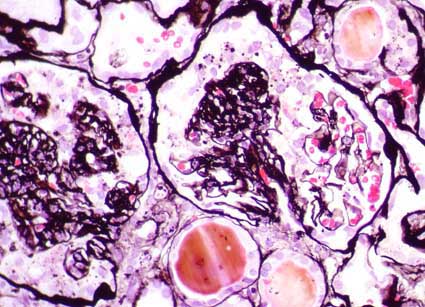

Figura 2.

Los cambios glomerulares suelen acompañarse, en esta glomerulopatía,

de extensos cambios tubulointersticiales. Tricrómico de Masson,

X100.

Figura 5.

La tinción de plata resalta el colapso del penacho (ver también

imágenes 6 y 7). Tinción de plata-metenamina, X400.

Figura 6.

Tinción de plata-metenamina, X400.

Figura 7.